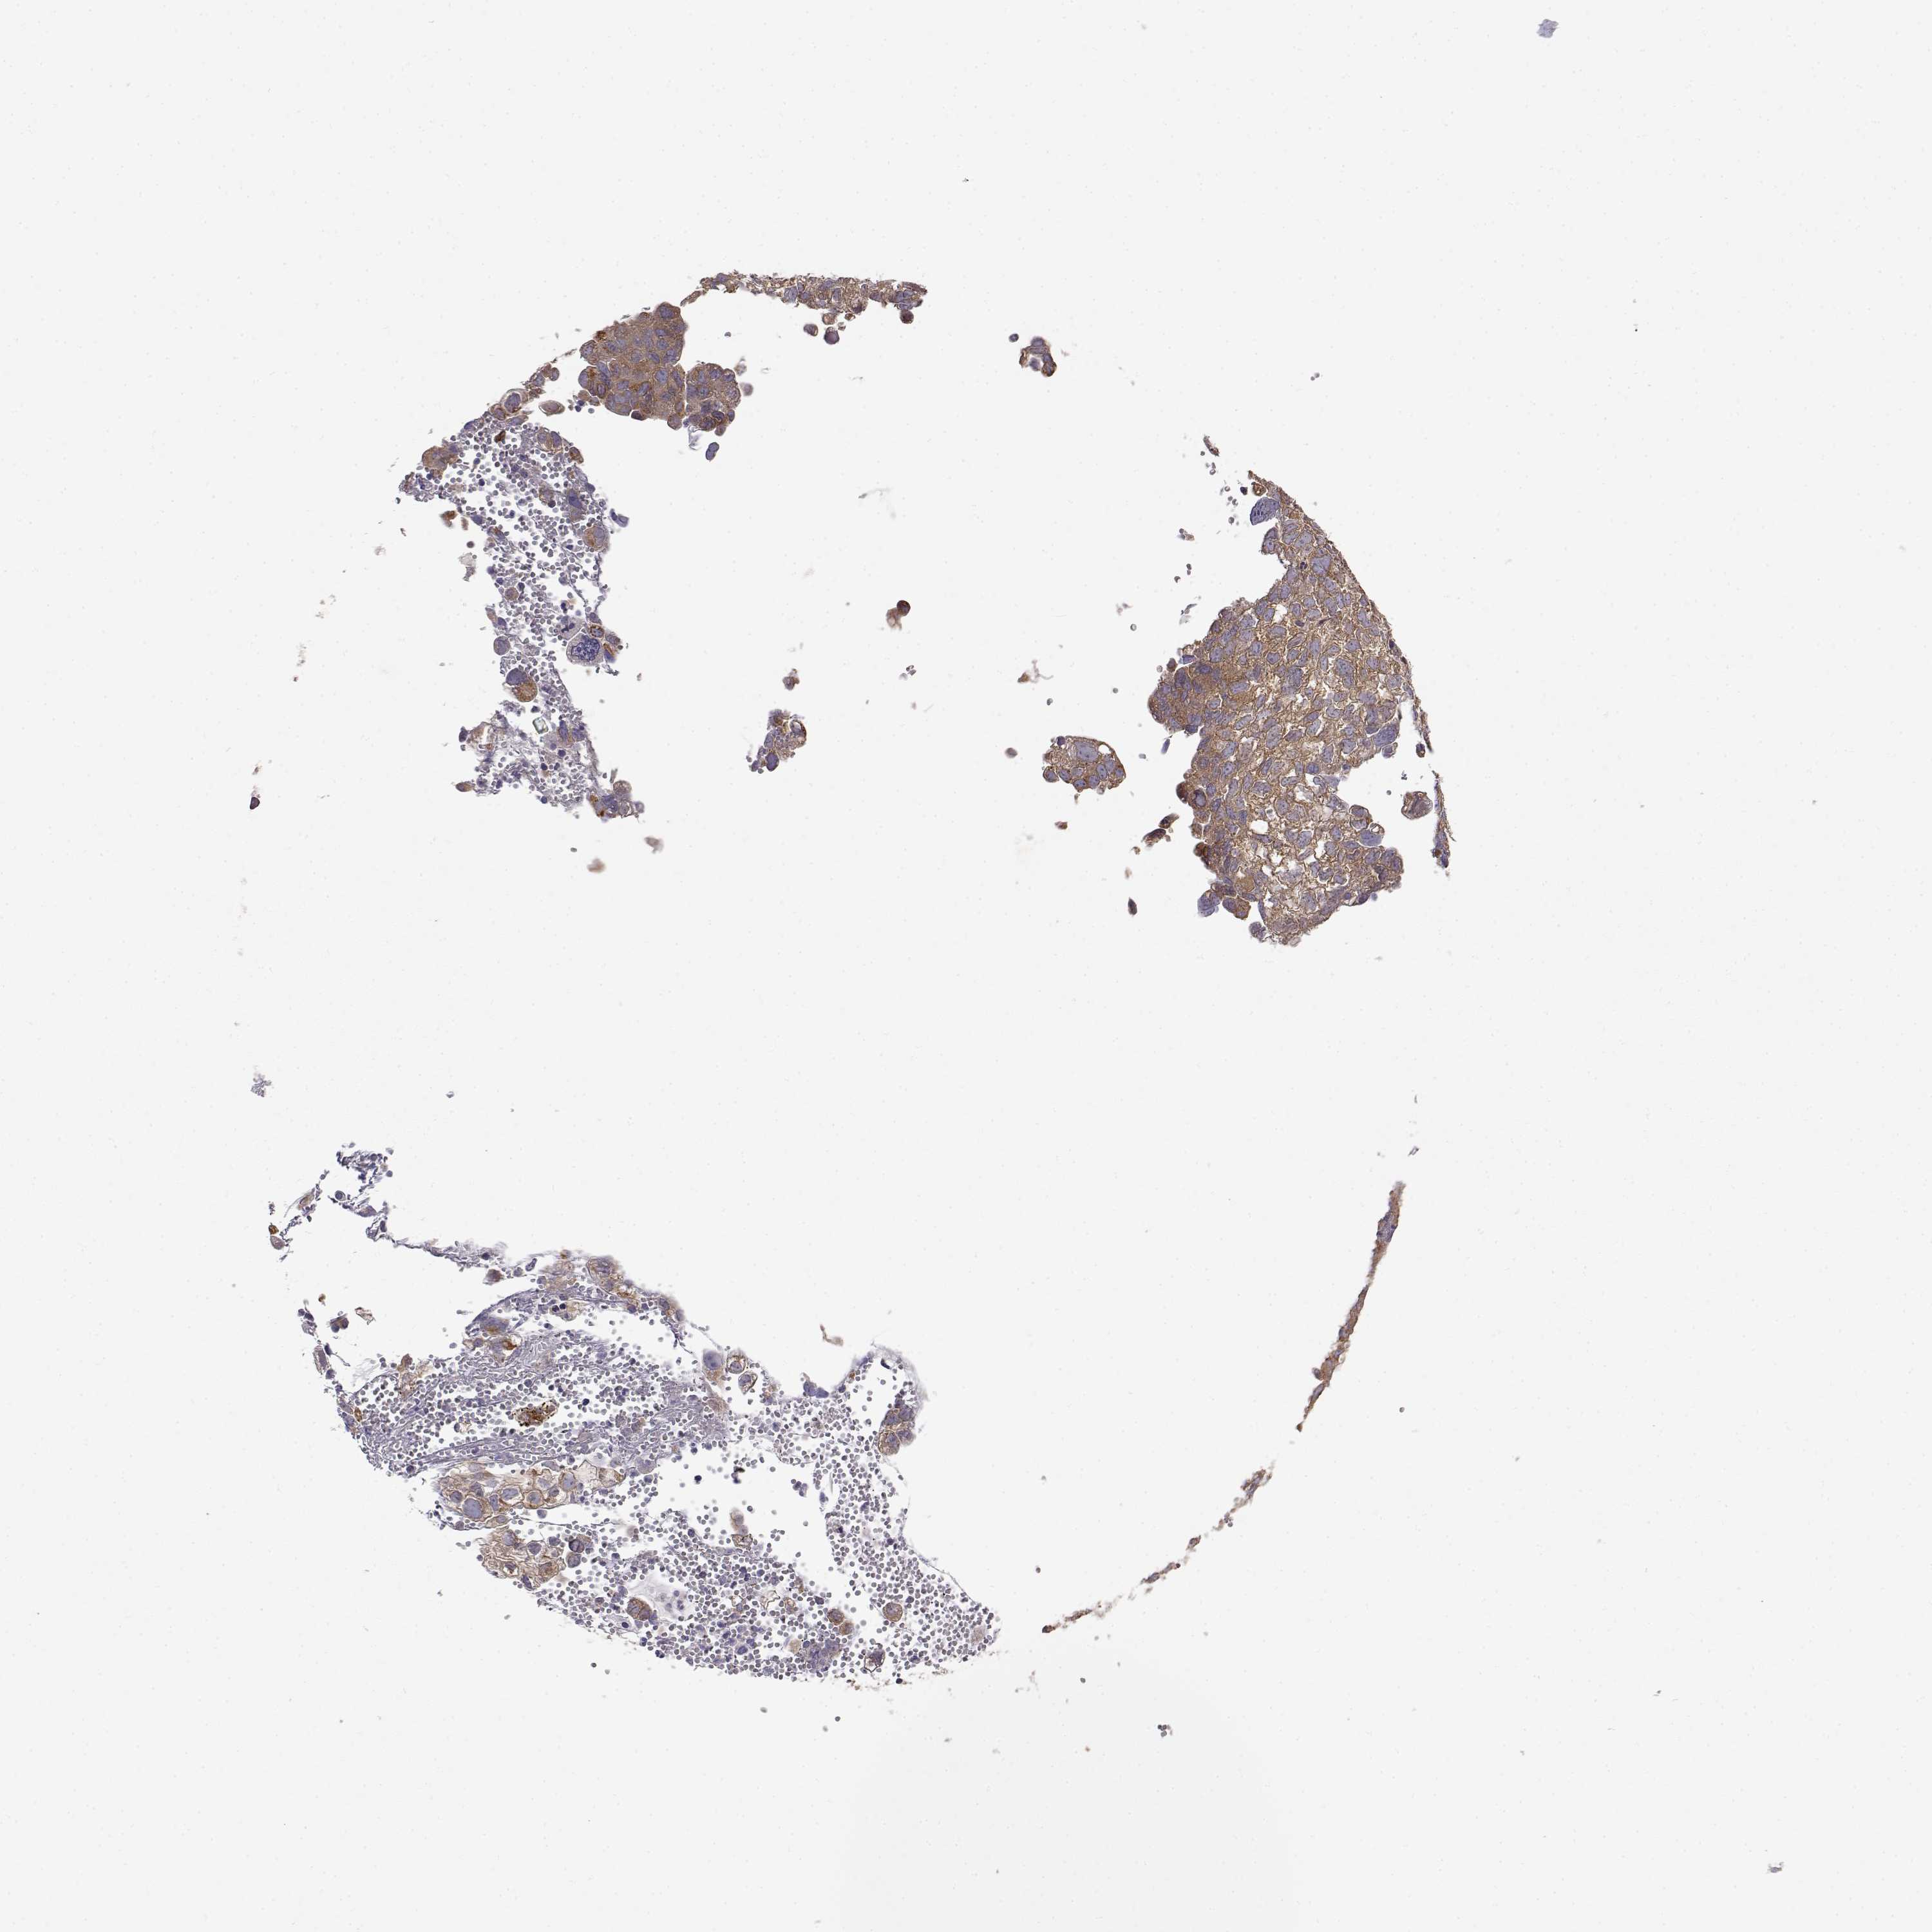

CERVICAL CANCER - Protein expressioni

A mouse-over function shows sample information and annotation data. Click on an image to view it in a full screen mode. Samples can be filtered based on level of antibody staining by selecting one or several of the following categories: high, medium, low and not detected. The assay and annotation is described here.

Note that samples used for immunohistochemistry by the Human Protein Atlas do not correspond to samples in the TCGA dataset.

Antibody stainingi

Antibody staining in the annotated cell types in the current human tissue is reported as not detected, low, medium, or high, based on conventional immunohistochemistry profiling in selected tissues. This score is based on the combination of the staining intensity and fraction of stained cells.

Each image is clickable and will lead to virtual microscopy that enables deeper exploration of all samples and also displays staining intensity scores, fraction scores and subcellular localization as well as patient and tissue information for each sample.

Antibody HPA073653

Staining

High

Medium

Low

Not detected

Intensity

Strong

Moderate

Weak

Negative

Quantity

>75%

75%-25%

<25%

None

Location

Nuclear

Cytoplasmic/membranous

Cytoplasmic/membranous,nuclear

Squamous cell carcinoma, NOS

Adenocarcinoma, NOS